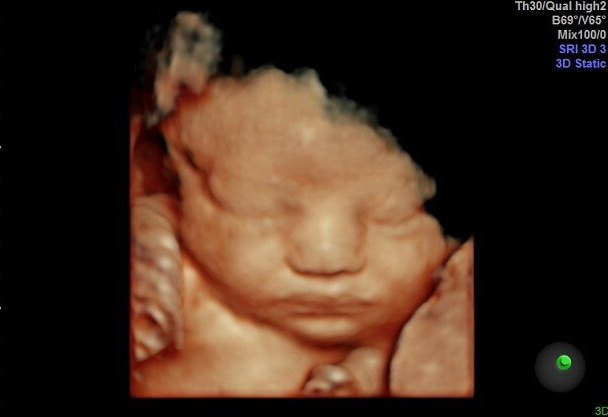

Gallery